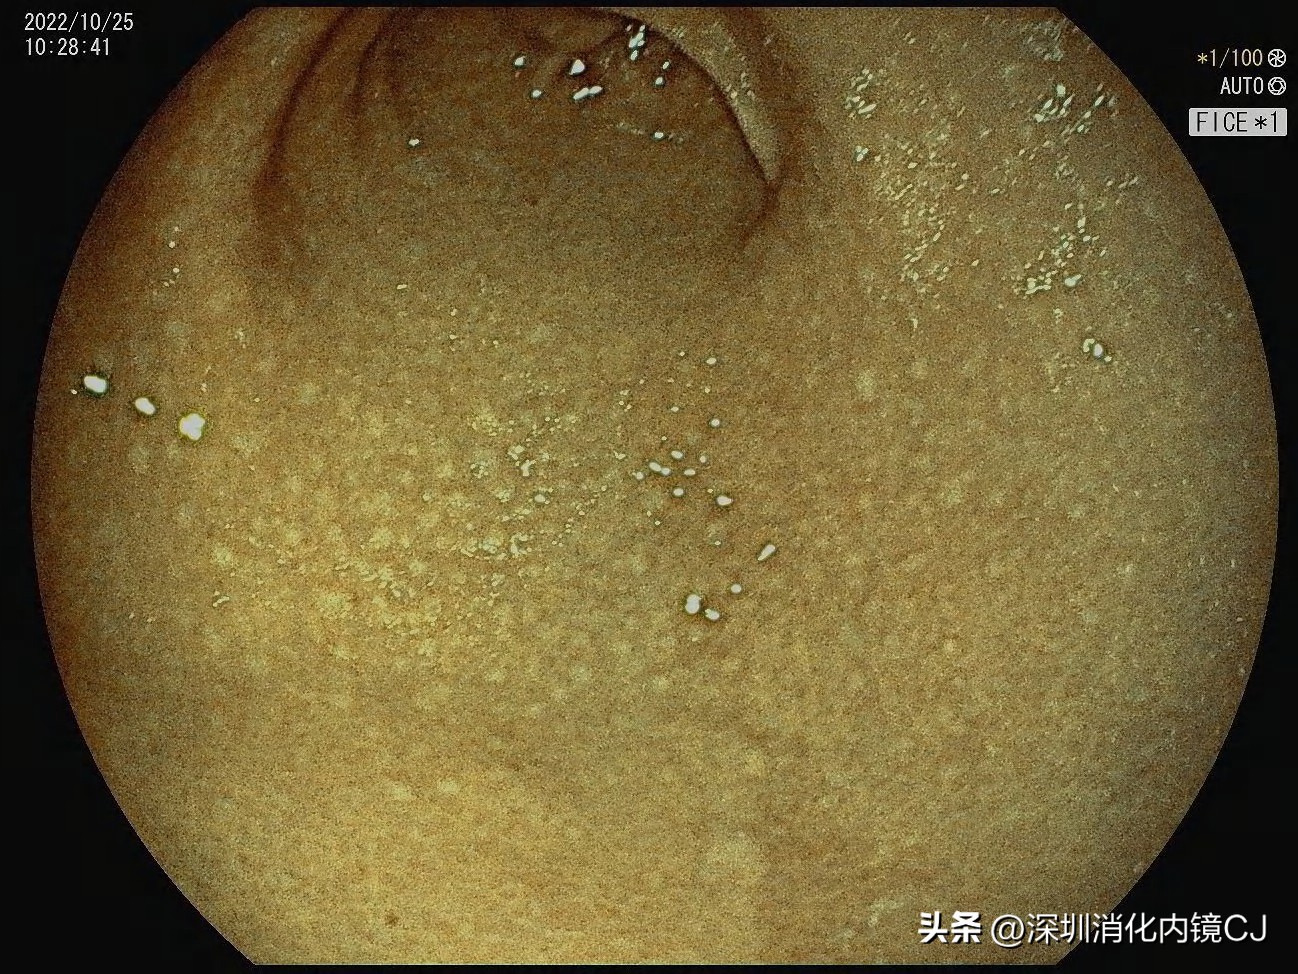

白光若隐若现

FICE染色后明显

靛胭紫染色后非常明显